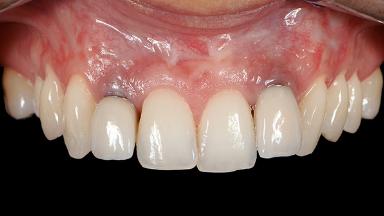

A 30-year-old woman was referred by her general dentist for evaluation of an esthetic complication related to previous implant treatment for congenitally missing maxillary lateral incisors. The patient’s chief complaint was the inadequate esthetic appearance of her smile. The case demonstrates the use of a combined approach to achieve optimal results. Two different flap designs - a tunnel technique and a coronally advanced flap - are employed based on the surgical objectives for the affected site.

Periodontal Plastic Surgery and Prosthetic Procedures to Treat Peri-Implant Soft-Tissue Dehiscences

Soft Tissue Grafting Yes